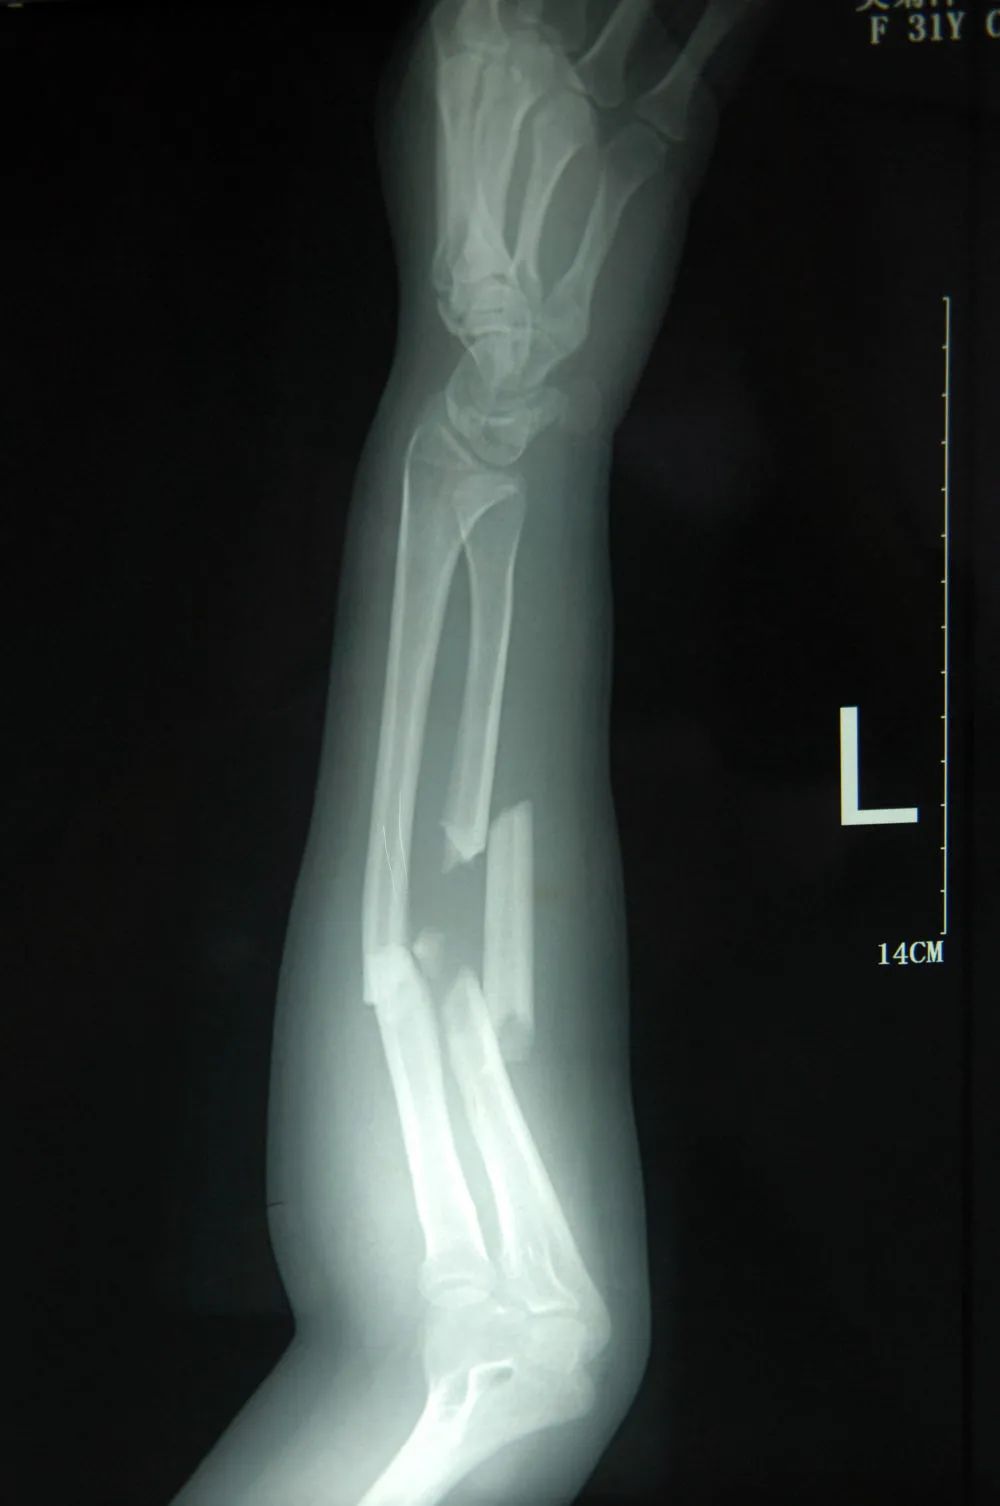

这是2011年7月3日拍摄的吴菊萍受伤左臂的X光片,医生诊断为手臂左尺桡骨多段粉碎性骨折。

当时,有热心网友做过计算:

一个2岁的孩子重30斤

从30米高的10层楼掉落

当吴菊萍的手臂

在接住她的那一秒

相当于接住了一个

重达300多公斤的物体